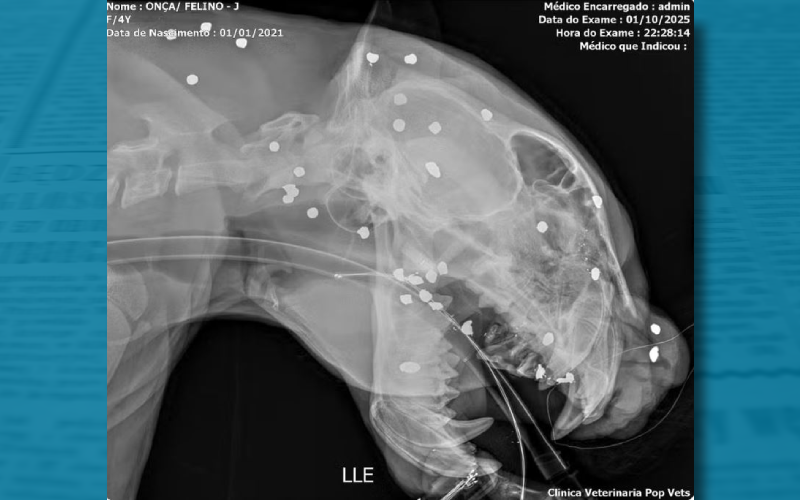

Raio-x mostra mais de 30 marcas de tiros no rosto de onça resgatada após passar horas a deriva em rio no AM. — Foto: Reprodução

Estilhaços de tiro atingiram o animal pelo rosto, cabeça e pescoço. Ela foi resgatada após ser vista nadando há horas no Rio Negro, em Manaus.

Um exame de raio-X feito após o resgate de uma onça-pintada nas águas do Rio Negro, em Manaus, mostrou que o animal foi atingido por mais de 30 estilhaços de tiro pelo rosto, cabeça e pescoço. A informação foi divulgada pela equipe de veterinários que presta assistência ao animal nesta quinta-feira (2).

Segundo a equipe que cuida do animal, além dos estilhaços causados por um tiro por arma de caça que levou na cabeça, a onça estava com dentes quebrados, ferimentos visíveis na cabeça e com debilidade intensa.

“A gente percebe que o tiro ele foi executado a distância. Ficou muito espalhado, não ficou um tiro concentrado em uma região. Se tivesse sido concentrado, o animal com certeza teria vindo a óbito. Então, a gente percebe que a pessoa deve ter atirado de longe, afim de fazer um afugentamento. Um tiro desse tipo no rosto, uma região extremamente sensível tem que ser avaliado de forma muito profunda”, explicou o biólogo e pesquisdor em felinos, Rogério Fonseca.